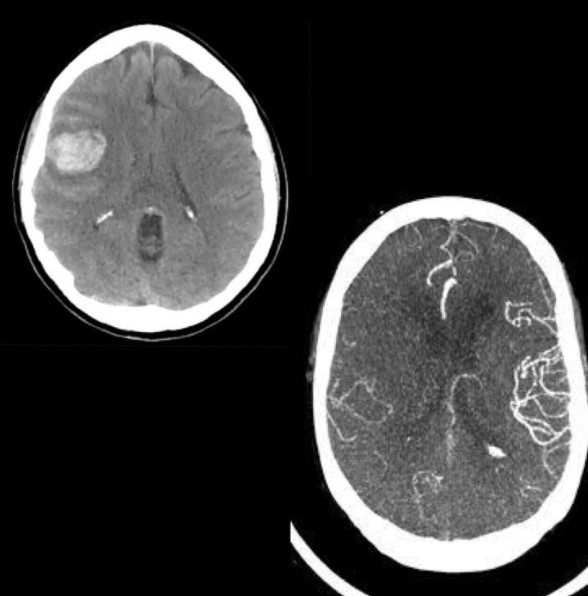

Q

Sangre en caso de que esté rota

Diagnóstico

• MAVs intraparenquimatosas (izq.) y subaracnoidea